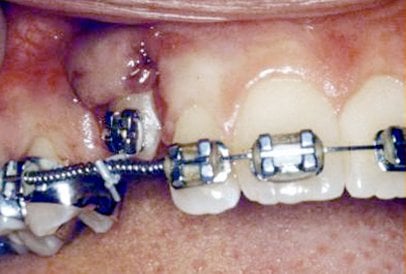

In cases where the eyeteeth will not erupt spontaneously, the orthodontist and oral surgeon will work together to get these teeth to erupt. Each case must be evaluated on an individual basis, but treatment will usually involve a combined effort between the orthodontist and the oral surgeon. The oral surgeon will expose and bracket the impacted eyetooth.

The goal is to erupt the impacted tooth and not to extract it. Once the tooth has moved into its final position, the gum around it will be evaluated. In some circumstances, there may be some minor “gum surgery” required.

Exposure and Bracketing of an Impacted Cuspid

What to expect from surgery to expose & bracket an impacted tooth

The surgery to expose and bracket an impacted tooth is a very straightforward surgical procedure that is performed in the oral surgeon’s office. For most patients, it is performed using laughing gas and local anesthesia. In selected cases it will be performed under IV sedation if the patient desires to be asleep, but this is generally not necessary for this procedure. If the procedure only requires exposing the tooth with no bracketing, the time required will be shortened by about one half. These issues will be discussed in detail at your preoperative consultation with your doctor.